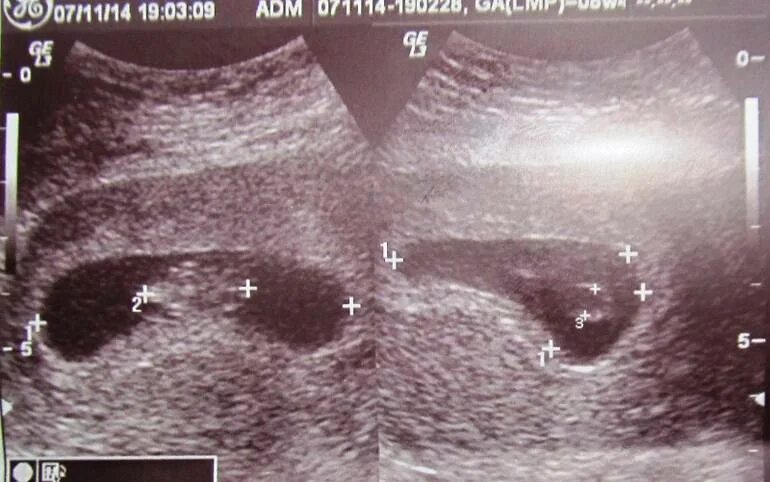

Фолликул после овуляции